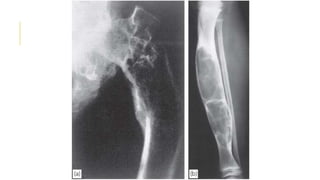

OSTEOSARCOMA

In its classic form, osteosarcoma is a highly malignant tumour

arising within the bone and spreading rapidly outwards to the

periosteum and surrounding soft tissues.

Osteosarcoma occurs predominantly in children and adolescents.

It may affect any bone but most commonly the long-bone

metaphyses, especially around the knee and at the proximal end of

the humerus.

Pain is usually the first symptom; it is constant, worse at night and

gradually increases in severity. Sometimes the patient presents with a

lump.

On examination there may be some swelling and local tenderness.

In late cases there is a palpable mass and the overlying tissues may

look inflamed

On x-ray

 Some tumours are entirely osteolytic, others show alternating

areas of lysis and increased bone density.

The tumour margins are poorly defined. Often the cortex is

breached and the tumour extends into the adjacent tissues.

Streaks of new bone appear, radiating outwards from the

cortex – the so-called ‘sunburst’ effect.

Where the tumour emerges from the cortex, reactive new bone

forms in the angle between periosteum and cortex (Codman’s

triangle).

OSTEOSARCOMA In its classicform, osteosarcoma is a highly malignant tumour arising within the bone and spreading rapidly outwards to the periosteum and surrounding soft tissues. Osteosarcoma occurs predominantly in children and adolescents. It may affect any bone but most commonly the long-bone metaphyses, especially around the knee and at the proximal end of the humerus. Pain is usually the first symptom; it is constant, worse at night and gradually increases in severity. Sometimes the patient presents with a lump. On examination there may be some swelling and local tenderness. In late cases there is a palpable mass and the overlying tissues may look inflamed

On x-ray  Sometumours are entirely osteolytic, others show alternating areas of lysis and increased bone density. The tumour margins are poorly defined. Often the cortex is breached and the tumour extends into the adjacent tissues. Streaks of new bone appear, radiating outwards from the cortex – the so-called ‘sunburst’ effect. Where the tumour emerges from the cortex, reactive new bone forms in the angle between periosteum and cortex (Codman’s triangle). Other imaging studies: -Radio-isotope scans may reveal skip lesions, but a negative scan does not exclude them. -CT and MRI reliably show the extent of the tumour. -Chest x-rays or pulmonary CT to detect lung metastases. DDx: Chronic bone infection, large gouty tophi and stress